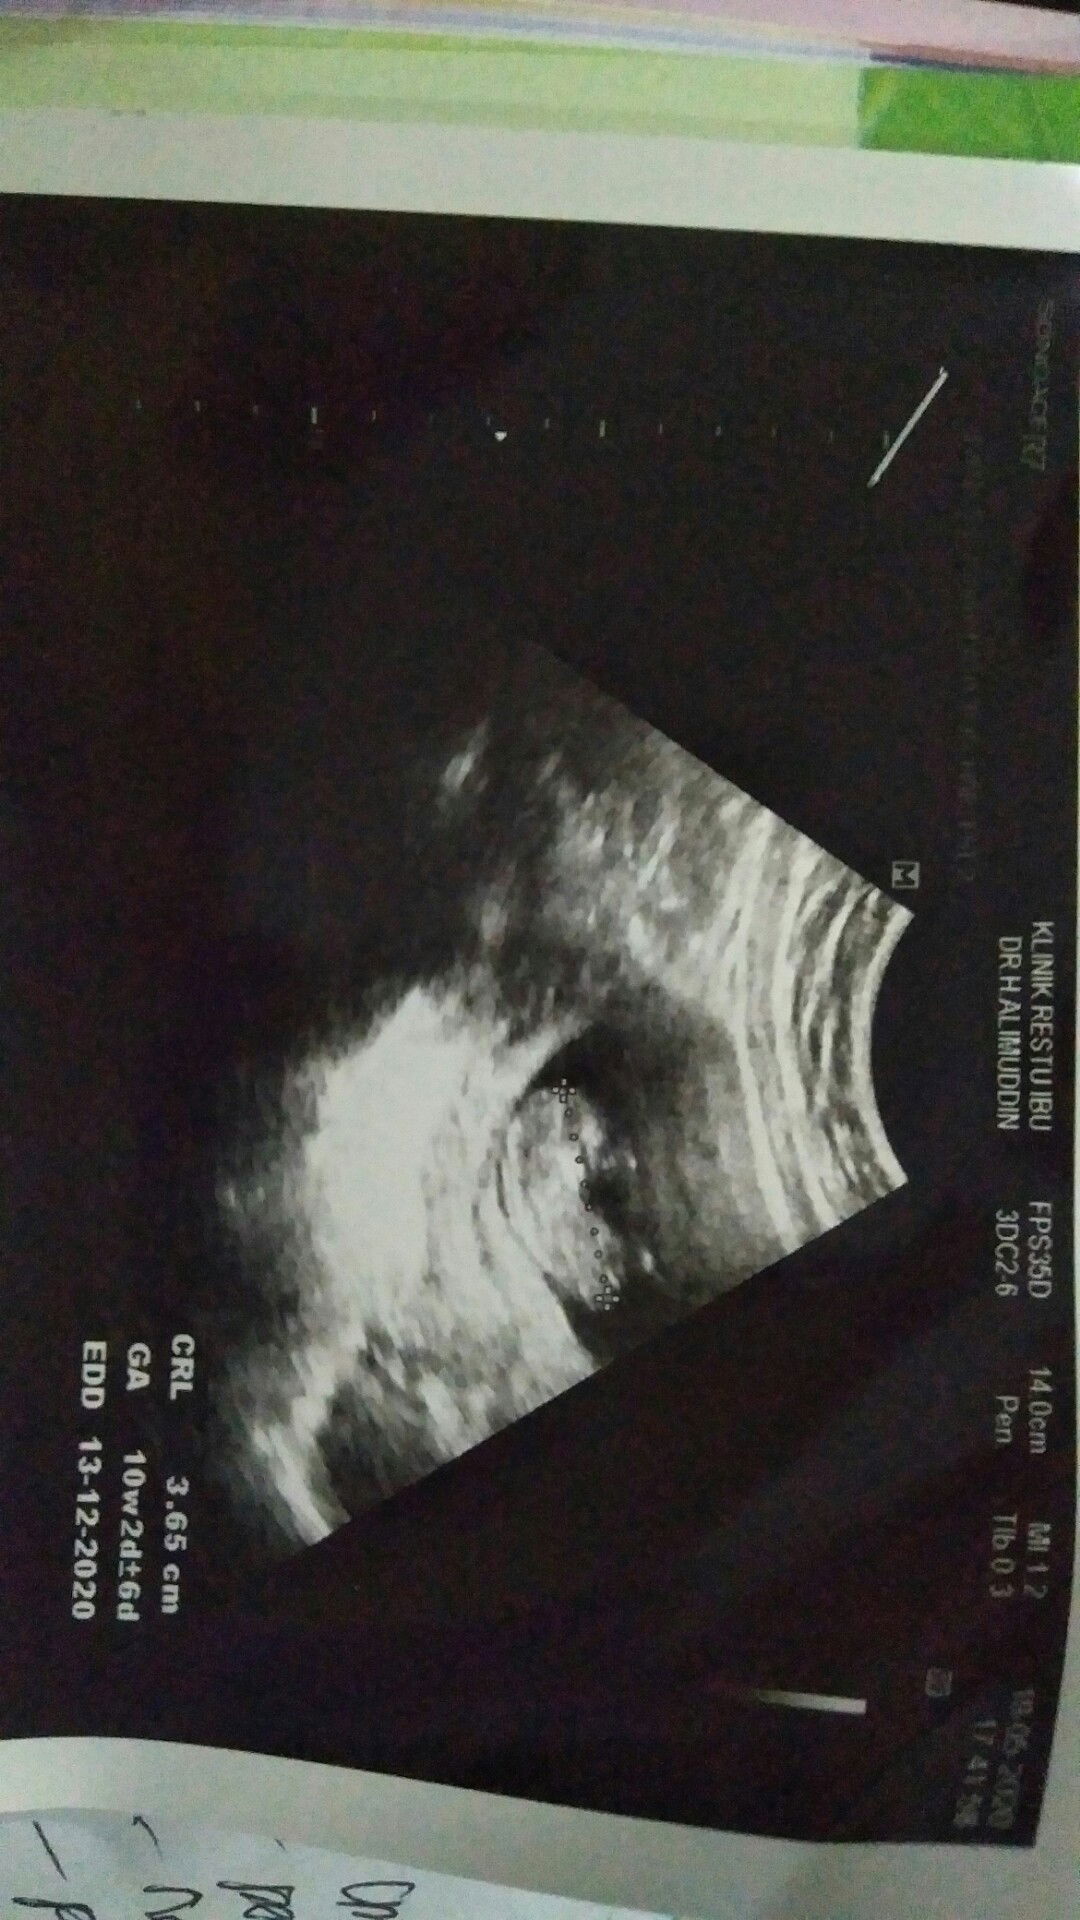

firts time USG

Alhamdulillah, khamilan prtama bunda , usia 10w 2d baru bisa kluar k klinik utk lihat prkmbangan di dede, sehat walaafiat kata dokterny ..? semoga bunda2 smua jga shat2 ya sma calon debayny.. Aamiin